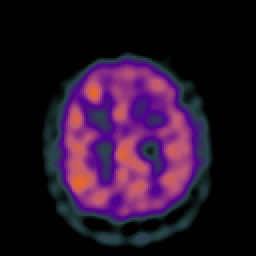

Vascular Malformation (at rest): perfusion SPECT study #1 -- Slice #19

[Home][Help][Clinical] Slice 19